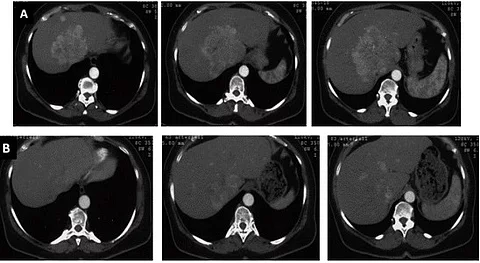

Hoffnung im Kampf gegen Tumore: Bösartige Leberzell- und inoperable Bauchspeicheldrüsentumore sowie gutartige Gebärmuttertumore können vielversprechend mit dem hoch-intensiven fokussierten Ultraschall (USg-HIFU) behandelt werden.